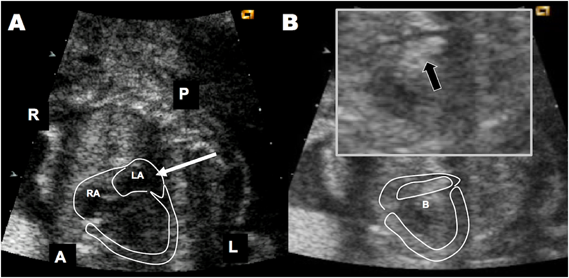

Fig. 3 A case of fetal Baloon Atrial Septoplasty

The fetus was diagnosed with hypoplastic left heart syndrome with highly restrictive foramen ovale at 22 weeks of gestation. A: At 23 weeks and 1 day of gestation, fBAS was performed under maternal local anesthesia and fetal muscular relaxation. The obstetrician determined the route of puncture from the left atrium under ultrasound monitoring based on fetal position. B: The balloon (Guidant Powersail 4 mm in diameter and 8 mm in length) was dilated at 20 atm (arrow). The patient underwent the Norwood procedure after birth followed by a Fontan operation at age 2 years (A: anterior, B: balloon, L: left, R: right, P: posterior).